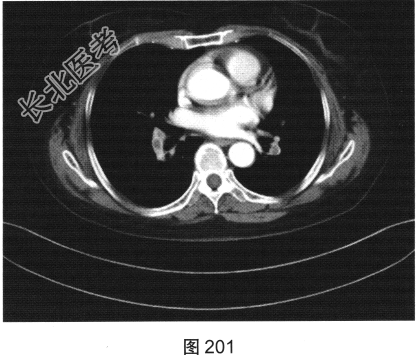

- 简答题4、该患者行颈部淋巴结活检,组织病理学结合免疫组织化学染色,考虑非霍奇金淋巴瘤弥漫大B细胞型。对该患者进一步行胸部、腹部、盆腔增强CT检查,如图200、图201所示。请问患者以上CT检查可见哪些影像异常?